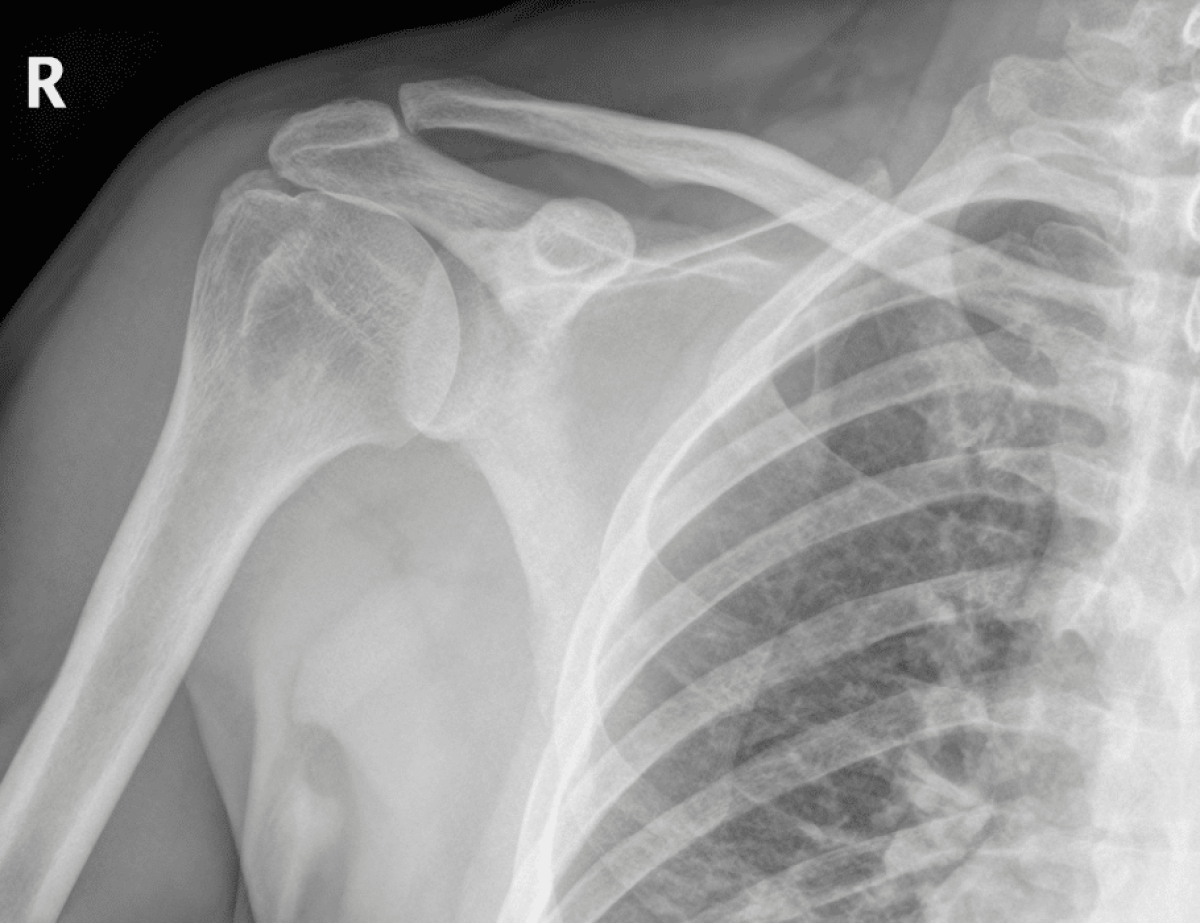

We worked to connect him with a proper doctor, an orthopedic specialist, who ordered an MRI revealing a torn rotator cuff. A month later, his surgery was approved, and his extensive rehabilitation process began.